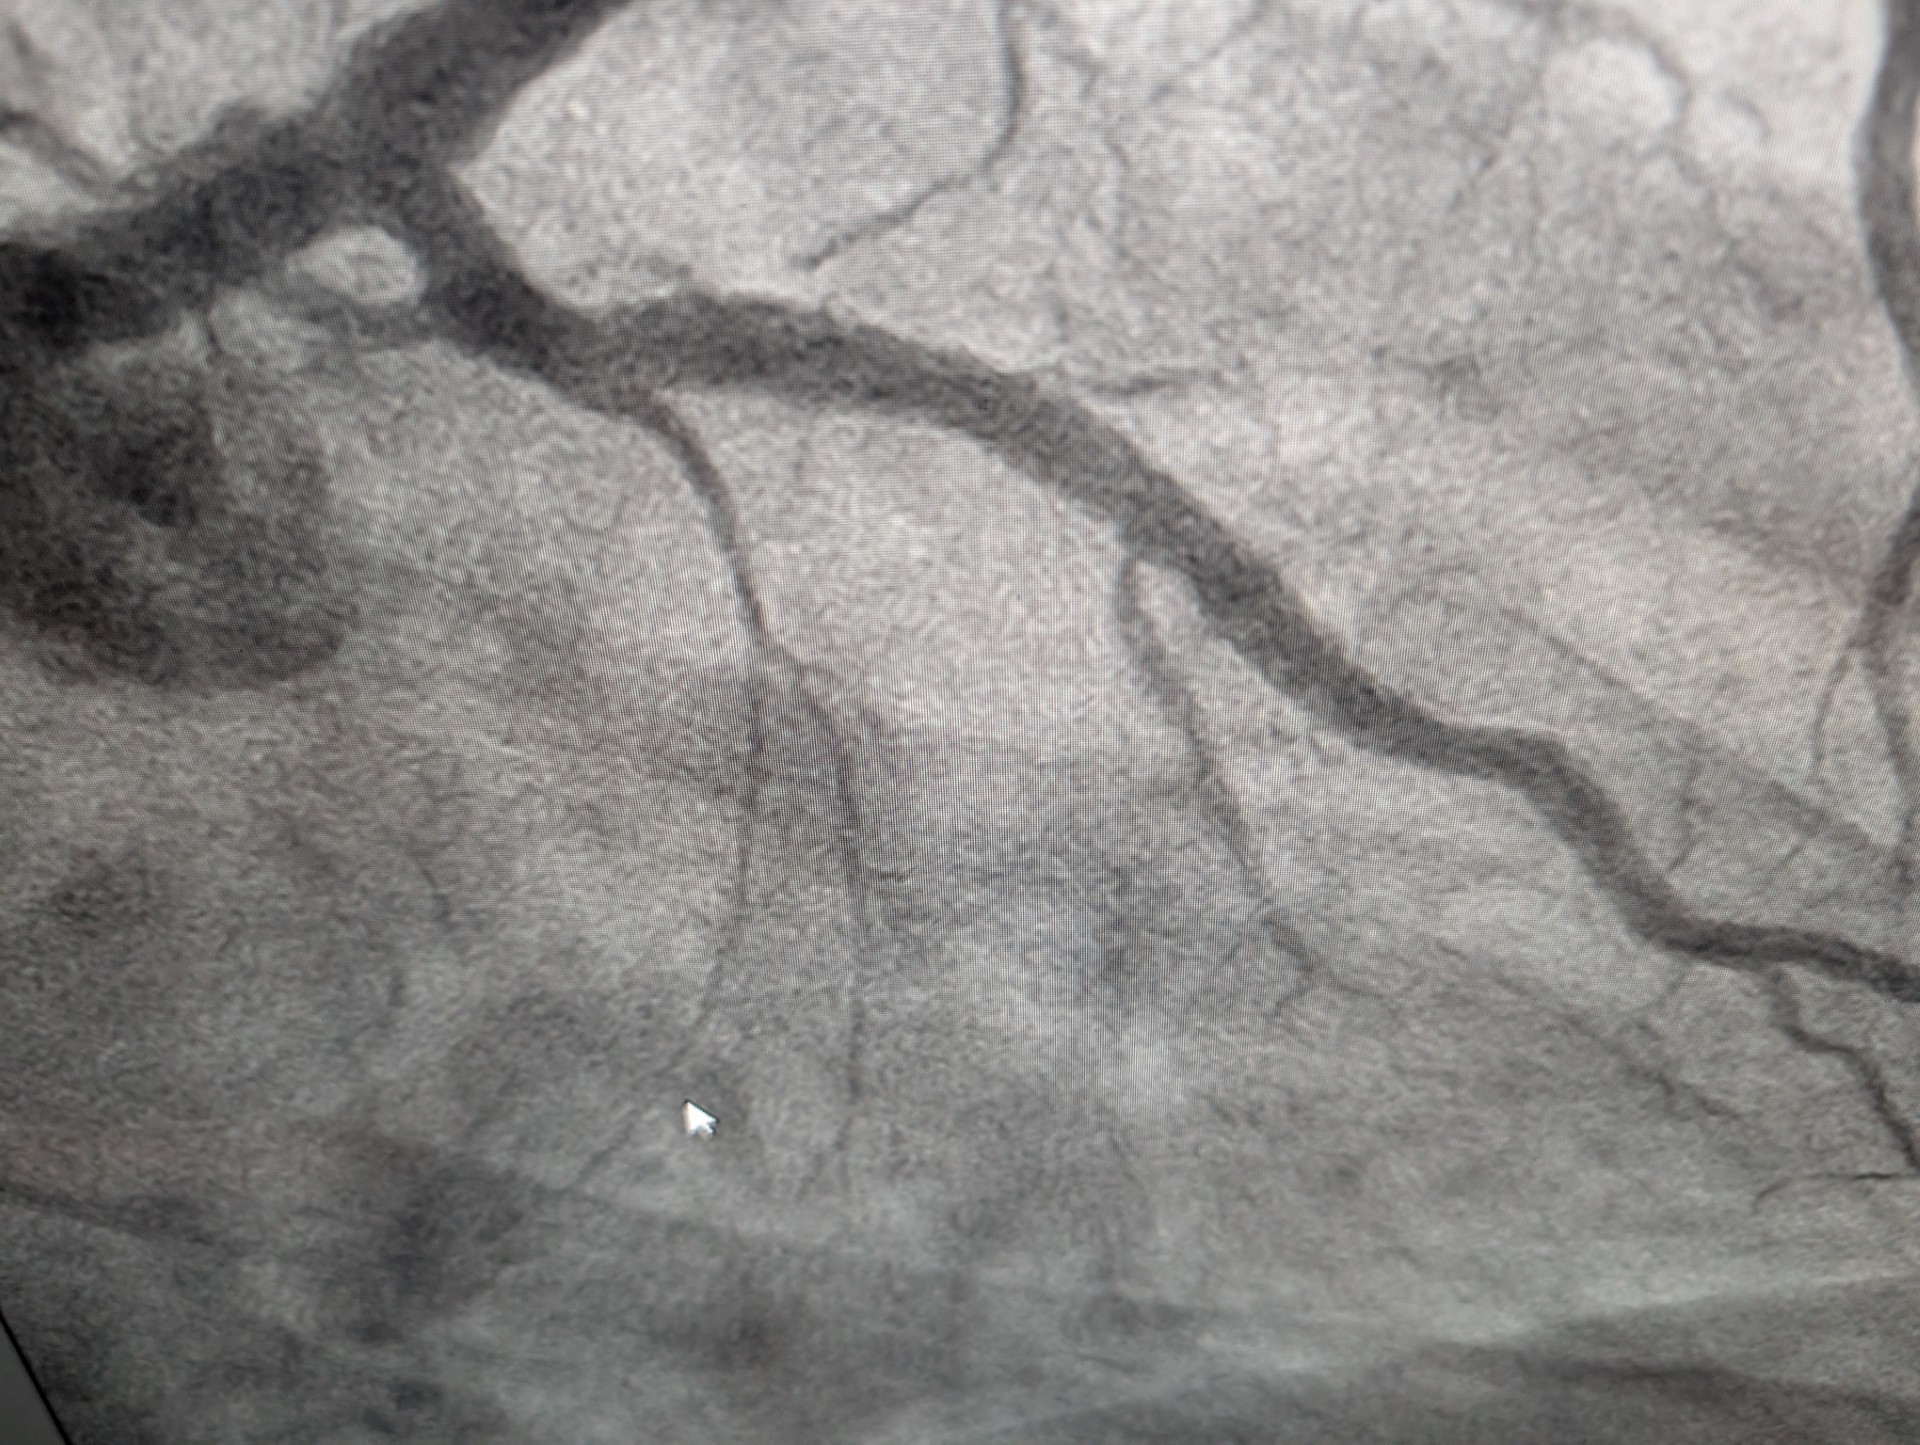

After: